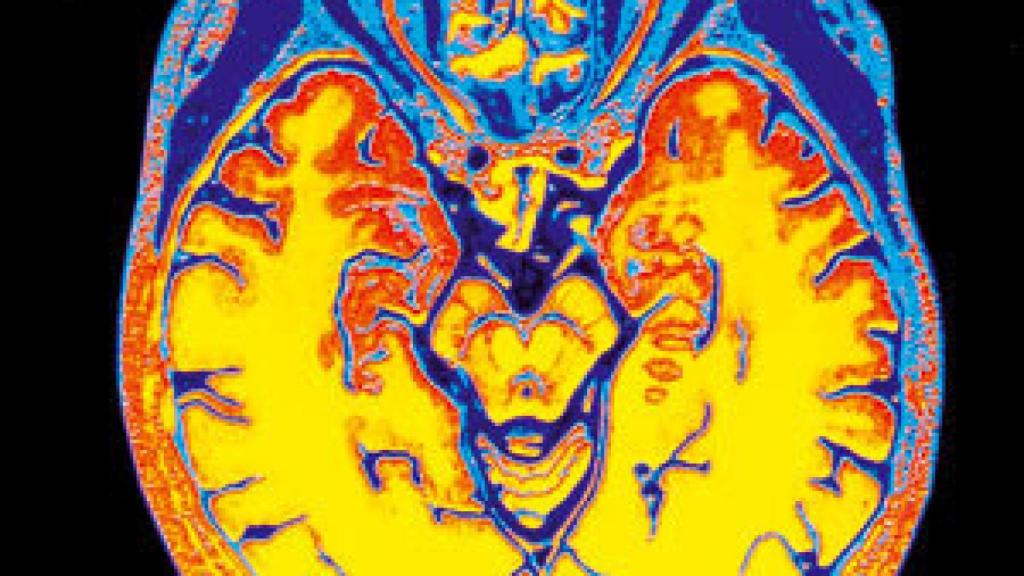

Escáner cerebral, de cielo y tierra (Phaidon)

Considerar el alma como mera metáfora de la conciencia de sí mismo, algo anclado en la realidad física del cerebro, disiparía en gran medida la espesa niebla que en general envuelve a estas cuestiones, en un ámbito que no admite la vía reduccionista ni las grandes simplificaciones. Ya he insistido en otras ocasiones en que ciertas parcelas científicas son de difícil o de imposible divulgación si el lector no adquiere una serie de arduos conocimientos previos. Éste es el caso de lo tratado en este libro, que supone un brillante esfuerzo por acercarse al lector común, quien a menudo debe conformarse con un acceso metafórico a la vanguardia del conocimiento. Damasio es consciente de este problema y resulta significativo que haya reformulado en forma poemática algunas de sus construcciones científicas: "Pero nadie sabía que las mentes existían, mucho menos los seres dentro de los cuales habían emergido ahora...". De la versión poética a la musical; en 2009 se ha estrenado en el Museo de Historia Natural de Nueva York una versión musical de Brain comes to Min, compuesta por Bruce Adolphe, interpretada por el violonchelista Yo-Yo Ma y dos percusionistas e ilustrada por imágenes cerebrales obtenidas por Hanna Damasio, internacionalmente reconocida por su atlas de imágenes cerebrales. Ante el libro y la pieza musical, interpretada esta última por un violonchelista con tal nombre, solo cabe esperar la máxima sublimación del Yo. El libro merece y recompensa el esfuerzo de su lectura.